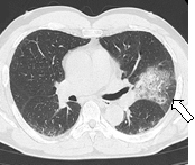

武漢ウィルスの肺炎患者を診察してきた医師がTV番組でCT画像での診断をする理由について話をしていました

その話によると、武漢ウィルスの肺炎患者のCT画像には、他の病原体の肺炎とは違う特徴が見られるそうです

一般的な肺炎では、5枚ある肺のうち通常1枚、多くても2枚の“内側”に白い放射状の影が見られるが、

武漢ウィルスの肺炎の場合には5枚全ての“外側の縁に沿って”白いもやもやした影が見られる

とのこと

この特徴がCT画像に見られれば、高い確率で武漢ウィルスによる肺炎だということがほぼ診断出来るので、PCR検査を確定のために行う、ということでしたよ

TVで観た記憶だが、新型コロナはCTでは特徴的な像になるらしい。

肺炎初期から両肺同時で、比較的弱い炎症が広い範囲に現れる。

この辺の情報は医師には伝わっているから、肺炎がコロナ由来かその他の原因かは

CTやMRIで非常に迅速に診断できるよね。